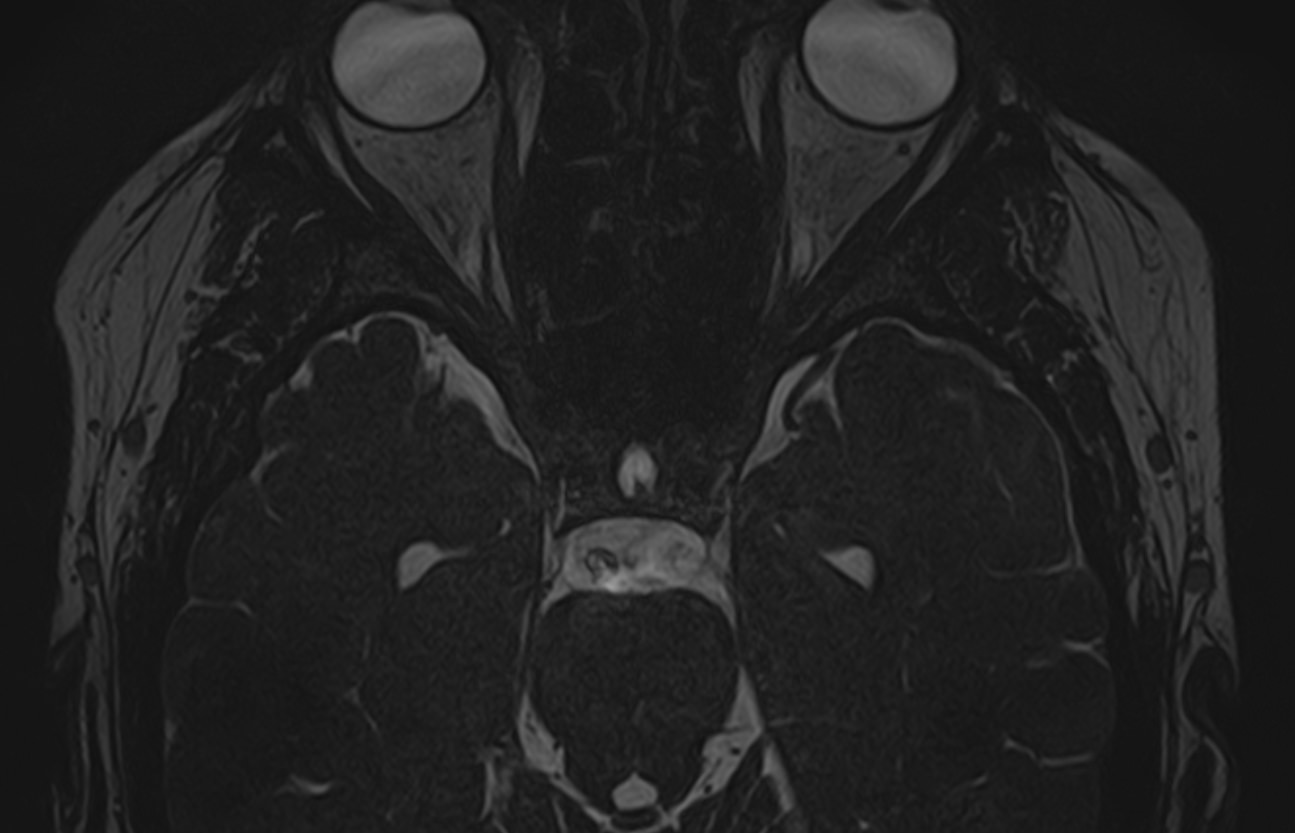

Для диагностики поражения черепно-мозговых нервов, а также оценки состояния окружающих их тканей и визуализации сосудистой сети головного мозга в клинике «Доступная медицина» проводится комплексное обследование МРТ головного мозга + черепно-мозговые нервы. Данное обследование включает в себя 2 протокола: стандартный — для оценки состояния всех структур головного мозга и специализированный — для изучения очагов поражения черепных нервов.

Оба исследования выполняются на современном высокопольном томографе экспертного класса TOSHIBA VANTAGE TITAN 1,5 Тесла, который использует разные режимы сканирования с толщиной среза от 1мм в различных плоскостях с последующей цифровой обработкой полученных данных для создания трехмерных изображений. Аппарат позволяет выявлять структурные изменения в веществе головного мозга и черепных нервах уже на начальной стадии, когда другие методы не дают результатов.

• патология нервов на фоне сосудистых проблем (вазоневральный конфликт — сдавление нерва близлежащим сосудом, также на фоне патологической извитости, аневризмы, сосудистой мальформации).